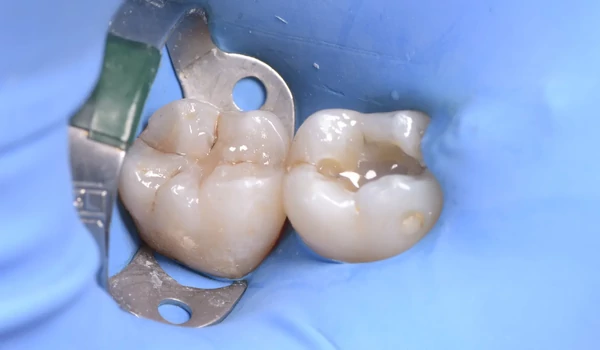

2. ábra A meglévő amalgámtömések eltávolítása utáni állapot. |

3. ábra Tipikus amalgámfestődés látható a nagyobb üreg alján. |